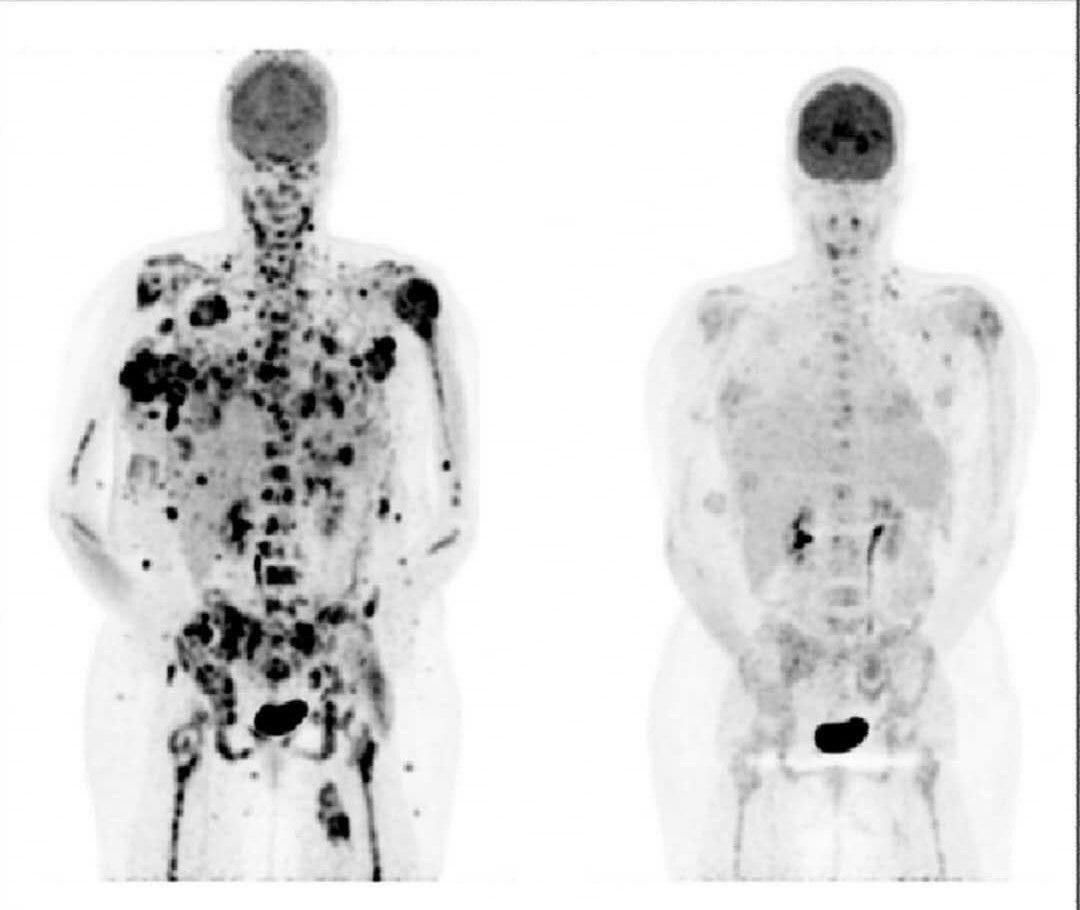

Как узнать есть метастазы

Как узнать есть метастазы 116 фото